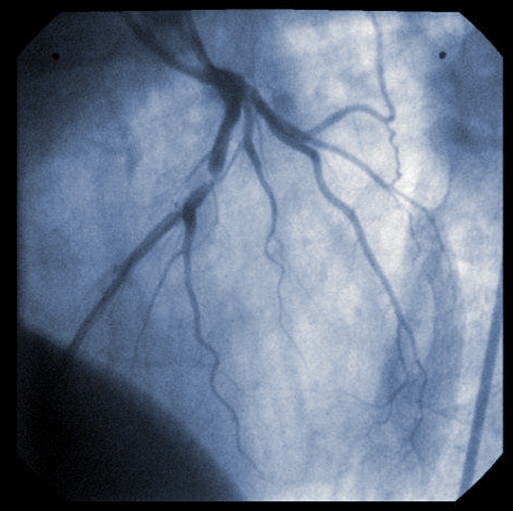

De nombreux patients admis à l’hôpital après une crise cardiaque de type STEMI (infarctus du myocarde avec élévation du segment ST) présentent d’importants blocages dans des vaisseaux sanguins autres que le vaisseau qui est directement responsable de la crise cardiaque. Les cardiologues tentent encore de trouver la meilleure stratégie pour traiter ces patients.

L’implantation d’une endoprothèse dans le « vaisseau incriminé » est appelée « intervention coronarienne percutanée » (ICP) primaire. Des chercheurs de l’Institut de cardiologie de l’Université d’Ottawa, dirigés par Juan Russo, résident en cardiologie, ont utilisé les dossiers des patients du registre STEMI de l’Institut pour voir s’il était sécuritaire d’implanter une endoprothèse dans les vaisseaux non incriminés après l’ICP primaire, mais avant que les patients quittent l’hôpital. Cette approche est qualifiée d’ICP par étape.